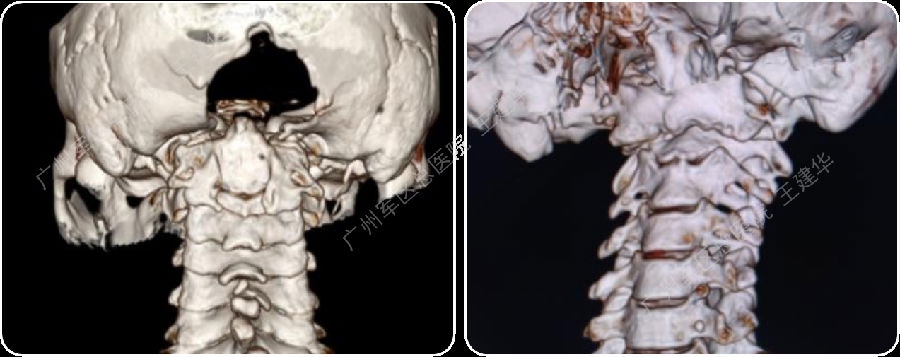

三维CT显示患者合并寰枕融合及C2/3融合,颅底凹陷

手术后2年复查的CT,显示侧块关节已经完全融合

颅颈椎序列恢复正常并骨性融合